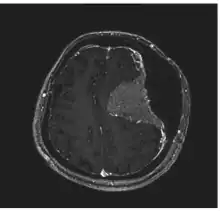

Hyperostosis is an excessive growth of bone. It may lead to exostosis. It occurs in many musculoskeletal disorders.

Image revealed a bilateral frontoparietal bone hyperostosis, particularly in the left side